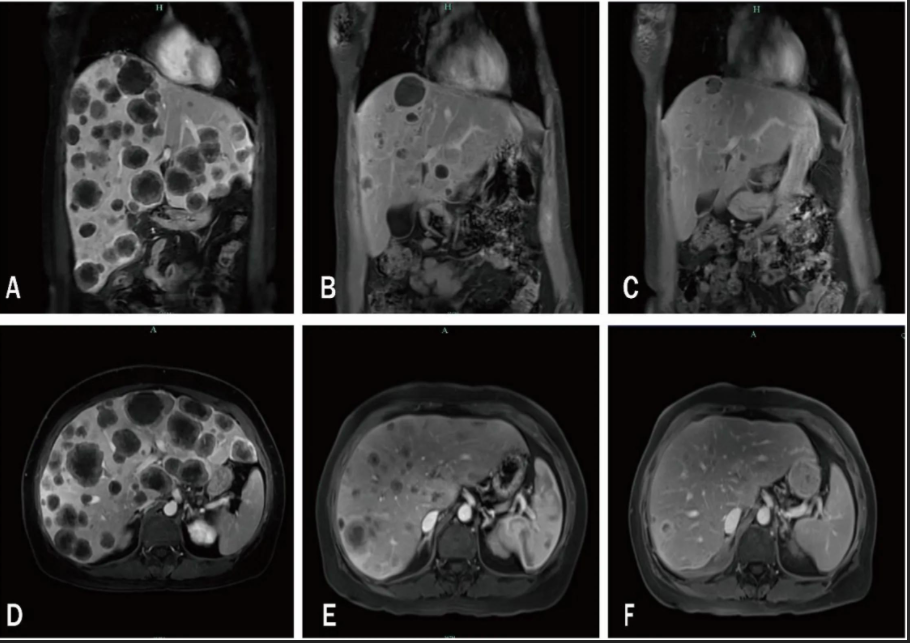

注:A, D:2024年4月9日,显示多处肝内转移;B, E:两次治疗周期后,2024年5月26日显示肿瘤显著退化;C, F:2024年7月31日随访显示肝转移负荷持续减少。

仅完成2个周期治疗后,2024年5月复查影像学显示肝内转移肿瘤负荷显著降低,同时血清糖类抗原125(CA125)、糖类抗原153(CA153)水平明显下降。治疗期间,患者出现尿频、尿急、尿痛伴血肌酐升高,临床高度怀疑为免疫介导性膀胱炎,遂停用帕博利珠单抗,改为SG单药维持治疗。

后续随访显示肝脏病灶持续退缩,患者生活质量良好,PFS延长至16.3个月,HVC被成功逆转。然而,因SG为自费药物且费用高昂,患者自行延长给药间隔、减少治疗频率,转而寻求口服中药治疗。